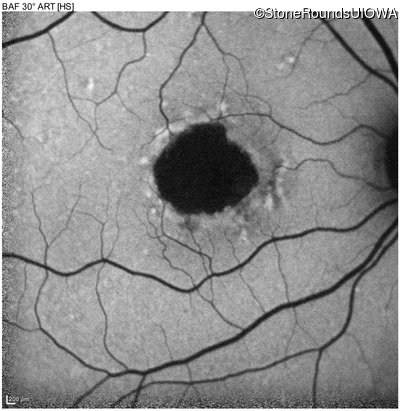

Infrared Fundus Photograph - Right - 20/40 -1

Exemplar